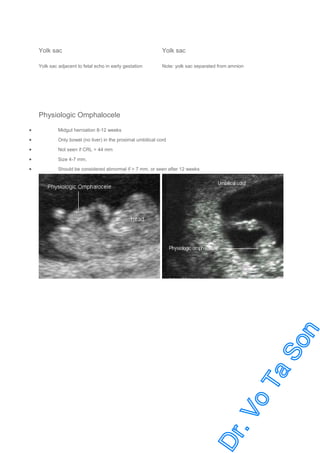

Yolk sac

Yolk sac adjacent to fetal echo in early gestation

Note: yolk sac separated from amnion

Physiologic Omphalocele

•

Midgut herniation 8-12 weeks

Only bowel (no liver) in the proximal umbilical cord

Not seen if CRL > 44 mm

Size 4-7 mm.

Should be considered abnormal if > 7 mm, or seen after 12 weeks

Prominent at 8-9 weeks

At 8 weeks

Physiologic omphalocele in abortus